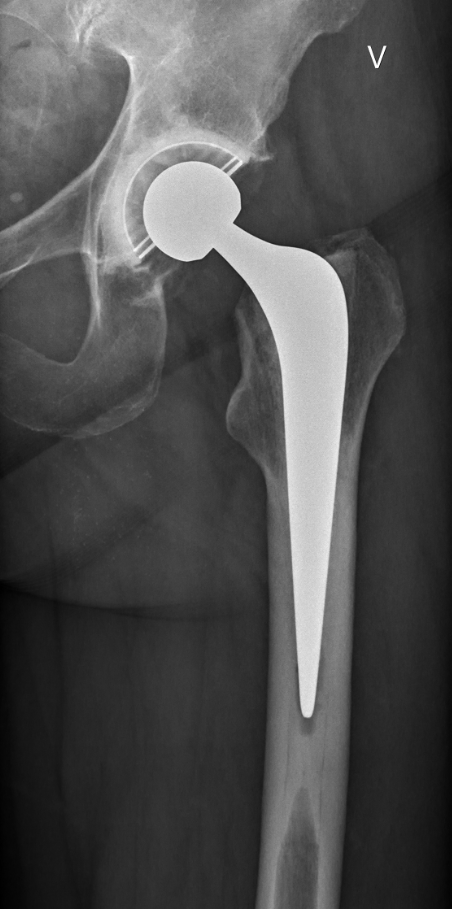

Røntgenbilde av hofteprotese

Røntgenbildet viser sementert hofteprotese i venstre hofte, som er standard behandling for lårhalsbrudd ute av stilling hos pasienter med godt funksjonsnivå. Bildediagnostisk avdeling, Nordlandssykehuset Vesterålen.

– Vi ser at på enkelte anbefalinger varierer det fra 0 til 100 prosent etterlevelse, som anbefalingen om å bruke sementert protesestamme ved behandling av hoftebrudd med protese. Dette kan ikke forklares ut fra forskjeller i pasientpopulasjonene, men oppfattes som et uttrykk for uberettiget variasjon. For å forstå og forbedre helsetjenestene, er det viktig å innta et fugleperspektiv for å få et mer helhetlig bilde.